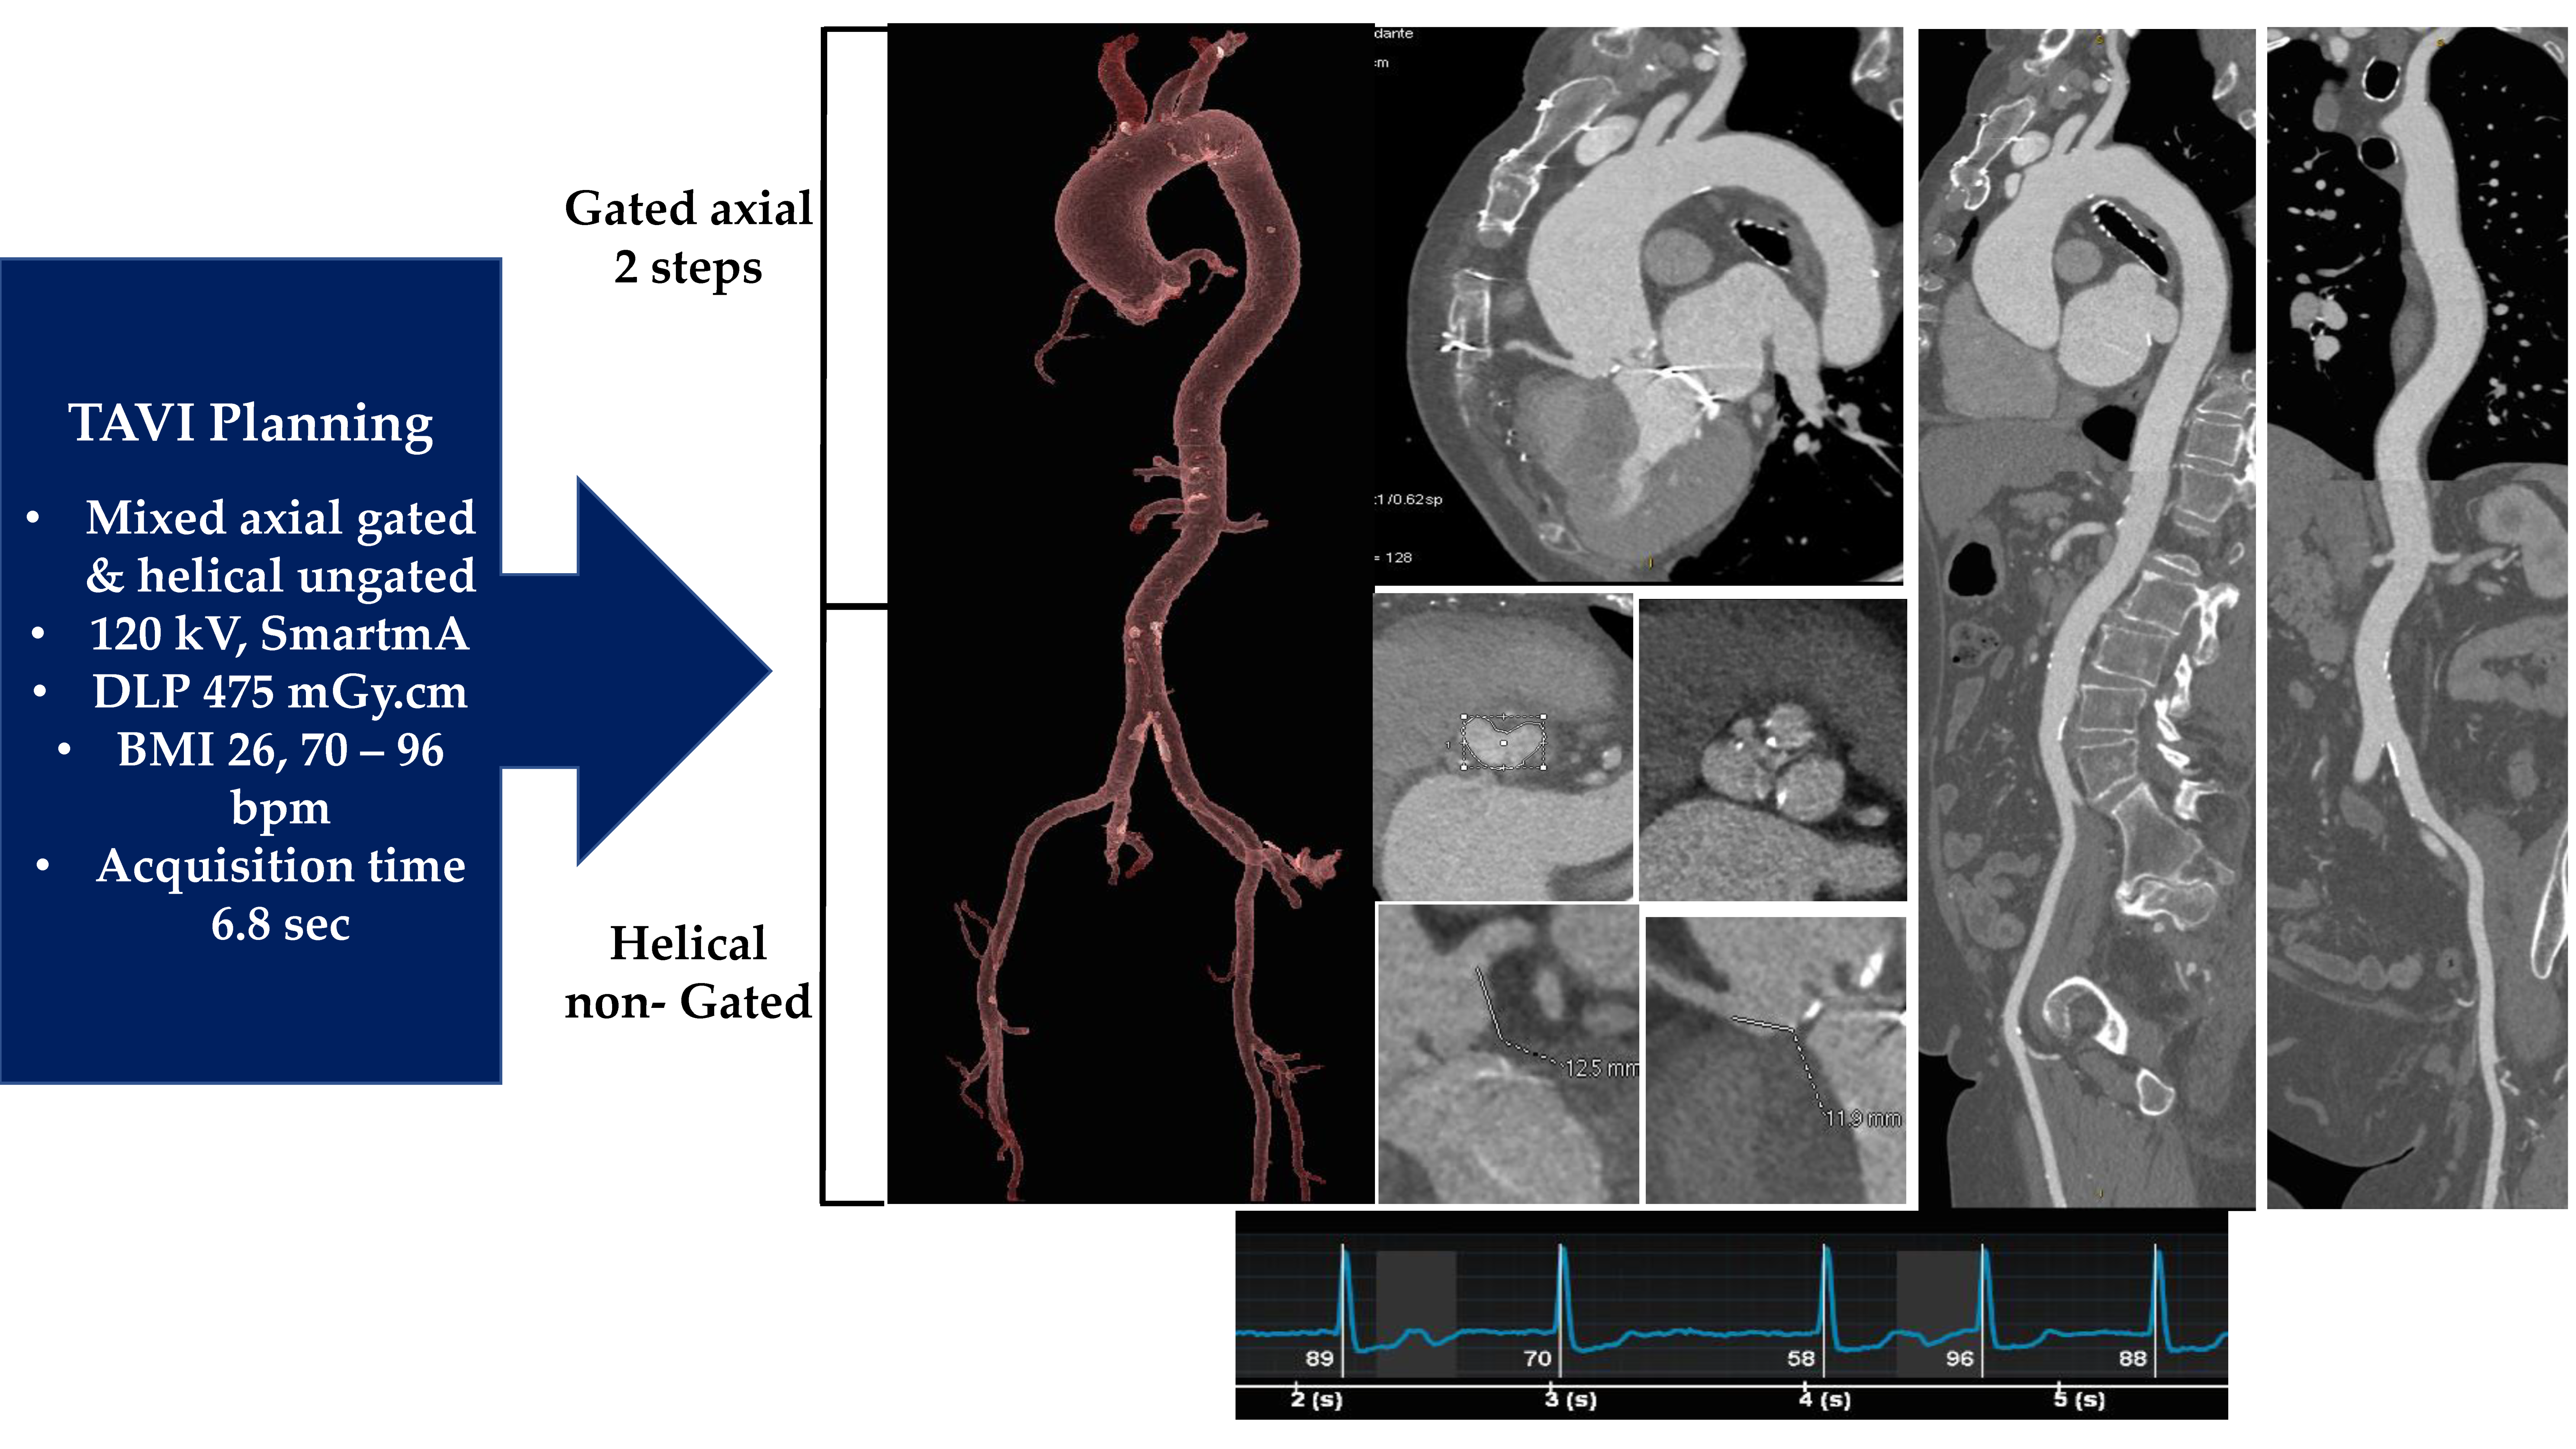

2.2. Medical Image Processing